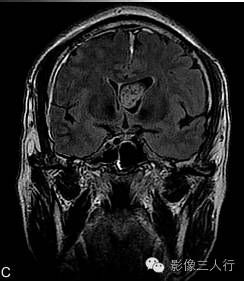

A.T2WI横断面;B.T1WI横断面;CFLAIR冠状面;D、E、F.增强横断面、矢状面、冠状面;G、H.CT平扫、增强;I.HE×100

肿瘤呈类圆形,边界清楚,位于左侧脑室前角及室间孔区,左侧脑室前角、三角部及左侧脑室后角扩张积水。MRI平扫T2WI(图A)肿瘤呈稍高信号,内见小范围高信号区;T1WI(图B)肿瘤呈等信号,内见低信号区;冠状面水抑制相(图C)肿瘤呈稍尚信号,内部原长T1长T2区信号呈低信号;增强扫描(图D~F)肿瘤强化不明显;CT平扫(图G)左侧脑室前角类圆形、边界清楚、较均匀等密度肿块,增强扫描(图H)强化不明显。